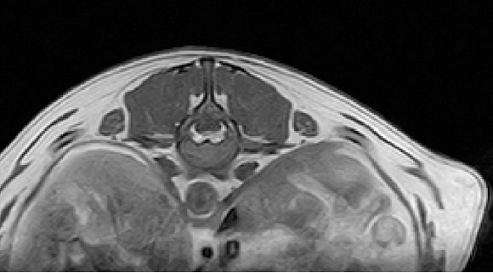

【画像診断】~ダックスフンド、雄10歳、グレート3の椎間板ヘルニア~

▲椎間板ヘルニアがあるMRI像T13-L1の頭側像、造影後のT1強調画像(キャミックに依頼)

はい、たいへん有効です。その椎間板ヘルニアの起こっている部位や、左右どちらに起こっているか、その他の異常(合併症等)があるかもこの検査で調べます。脊椎の診断はMRI検査が最も理想的な検査法ですが、撮影時間や費用、設備の有無等に制約があるます。より実用的な検査としてはCTも良い検査法になりますが約15%でその部位に石灰化が起こってないとわらない場合がありますが、そんな場合は造影をすれば判定できます。MRIの場合、椎間板の変性はT2強調像、矢状断面像で最も良く観察、でき脊髄腫瘍、椎体腫瘍等、脊髄髄内の検出にも理想的な検査です。多くの腫瘍はT1強調像では脊髄と比較すると等信号から低信号にT2強調像では高信号となります。